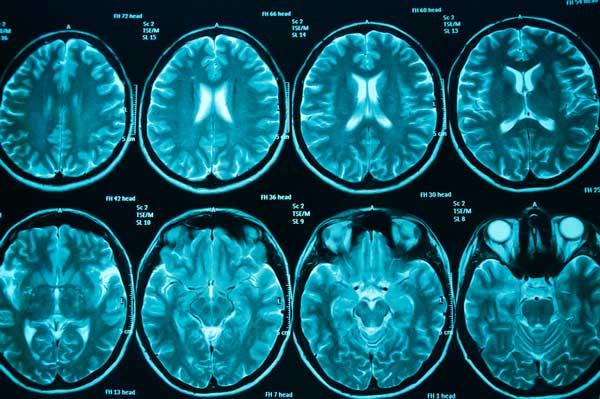

Để đánh giá các triệu chứng trên có phải dấu hiệu ung thư não hay là các bệnh về thần kinh khác và giúp đưa ra phác đồ điều trị phù hợp, phương pháp thường áp dụng trong việc chẩn đoán xác định các bệnh về não nói chung cũng như các khối u não nói riêng gồm có:

- Tìm hiểu bệnh sử và thăm khám kỹ lưỡng các triệu chứng

- Chẩn đoán hình ảnh: Chụp CT scan hoặc MRI để phát hiện khối u.

Việc chẩn đoán và điều trị khối u não có thể rất phức tạp và nhiều bệnh nhân có thể cảm thấy choáng khi lần đầu được chẩn đoán mắc khối u não. (Ảnh: The Brain Tumour Charity)

Chẩn đoán bệnh ung thư não cũng được thực hiện bằng cách kết hợp mô học với các phương pháp hình ảnh như chụp cắt lớp vi tính (CT) và chụp cộng hưởng từ (MRI) cùng với các dấu hiệu sinh học. Nhận biết các dấu hiệu ung thư não có thể kịp thời chữa trị để tăng khả năng sống sót.